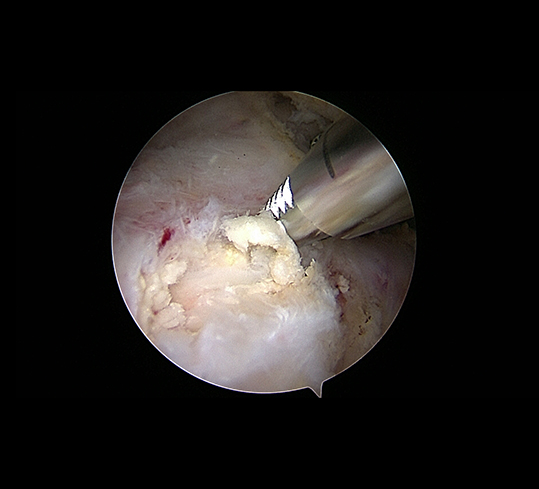

Führt dies nicht zum gewünschten Erfolg und die Beschwerden persistieren so kann die Kalkablagerung arthroskopisch entfernt werden – ein schonender Eingriff, der oft zu einer raschen Beschwerdelinderung führt.